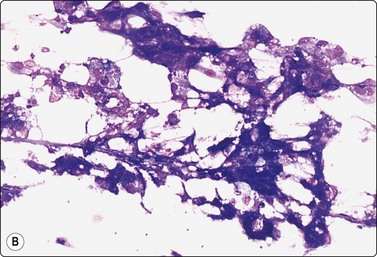

image image image

Fig. 7.19 Fat necrosis

(A) Postoperative fat necrosis. Necrotic tissue, debris and macrophages; fragment of adipose tissue upper right (MGG IP); (B) Fragments consisting of altered adipocytes, macrophages and fat droplets (MGG, IP); (C) Several multinucleated histiocytes with foamy cytoplasm (MGG, HP).

Criteria for diagnosis

A ‘dirty’ background of granular debris, fat droplets and fragments of adipose tissue,

Foamy macrophages, multinucleated giant cells and adipocytes with bubbly cytoplasm,

Chronic inflammatory cells,

Absence of epithelial cells.

Postoperative changes in response to prior surgical excision or biopsy give similar findings. Fat necrosis is always in the differential diagnosis of nodules in scars or chest wall after surgery, particularly mastectomy. Vigorous or repeated palpation of breast tissue or previous aspiration of the site can result in the same changes. The aspirate is usually scanty, sometimes of oily fluid, and consists mainly of fat with some foamy macrophages or altered, vacuolated adipocytes and multinucleated histiocytic giant cells. The untidy background of granular debris represents the actual necrosis and is the most specific diagnostic feature (Fig. 7.19A,B).

The dispersed presentation of macrophages, particularly if the cytoplasm is dense or nonvacuolated and the nuclei are large with an irregular shape and prominent nucleoli, may mimic a malignant cell pattern, particularly in air-dried MGG smears. Multinucleate forms and foamy cells with similar morphology are helpful in preventing error (Fig. 7.19C).102 Conversely, some carcinoma cells may resemble macrophages. Immunostaining or excision is sometimes necessary.